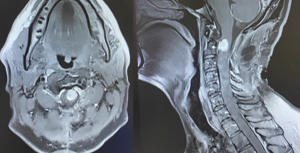

A rare case of spinal atypical teratoid/rhabdoid tumor is presented in an adult man after presenting with neck pain and bilateral upper extremity paralysis.